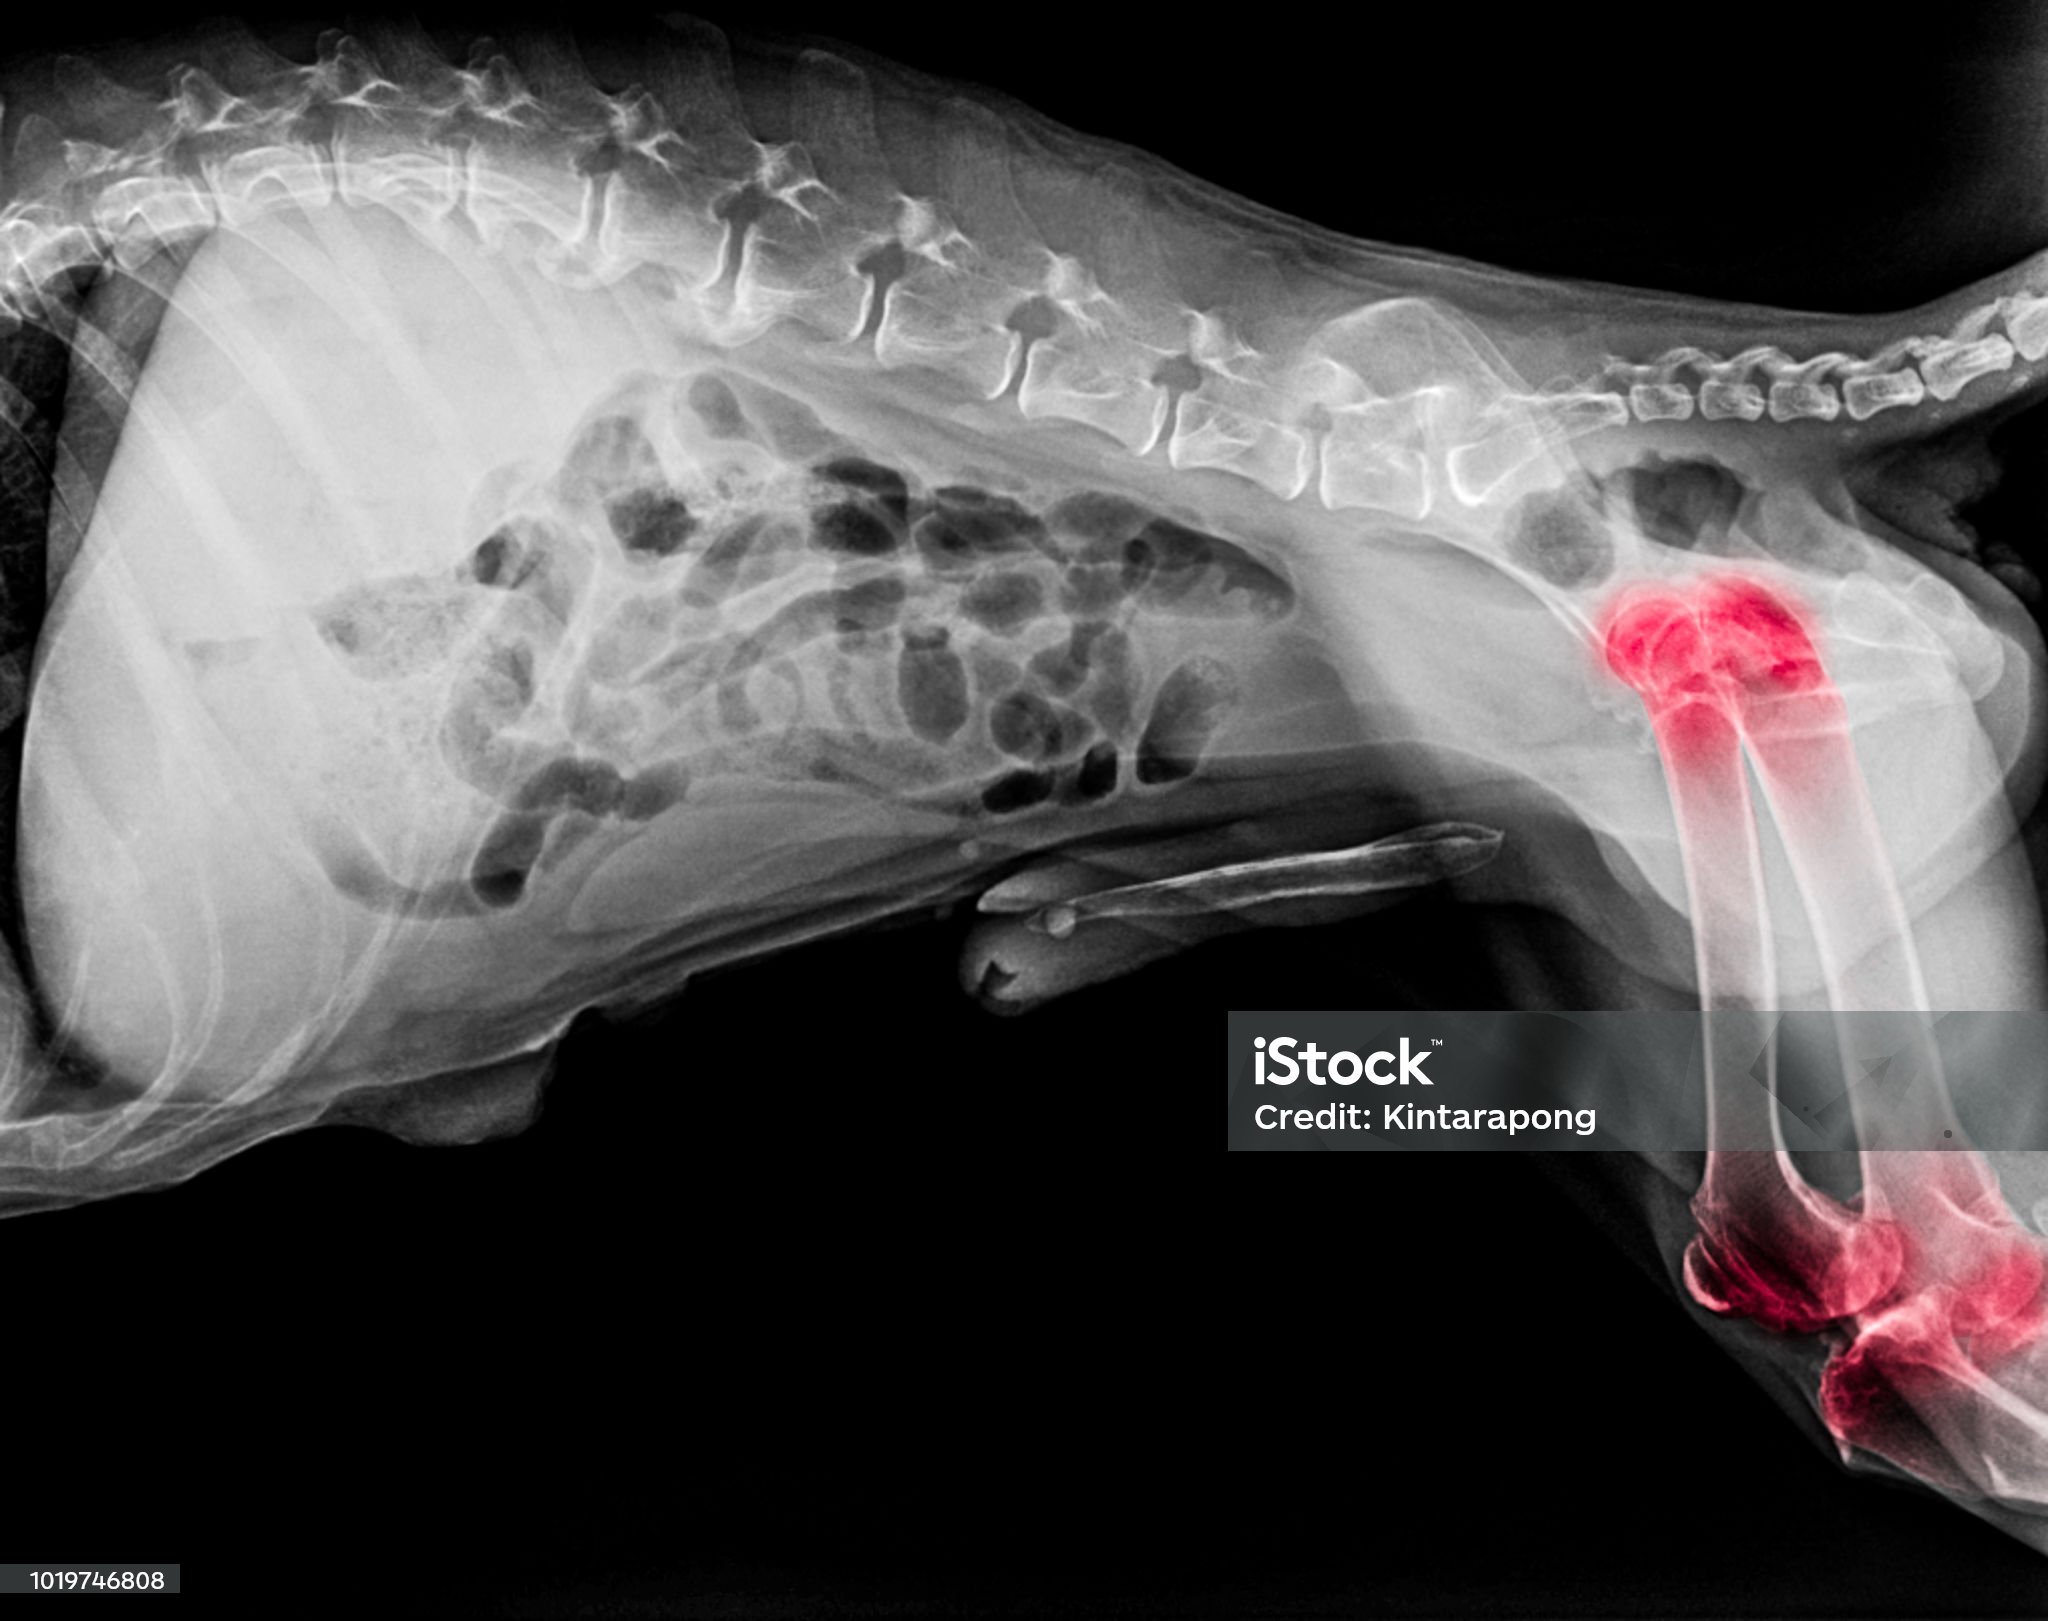

강아지 고관절 탈구는 엉덩이 관절(고관절)을 구성하는 뼈가 정상 위치에서 벗어난 상태를 의미한다. 주로 대퇴골이 골반의 관절구에서 빠져나가면서, 통증과 보행 이상, 운동 장애를 유발한다. 이 질환은 특히 소형견, 노령견, 선천적으로 관절이 약한 견종에서 자주 발생한다.

위와 같은 증상이 나타난다면 즉시 동물병원에서 엑스레이 촬영 및 전문 진단을 받아야 한다.